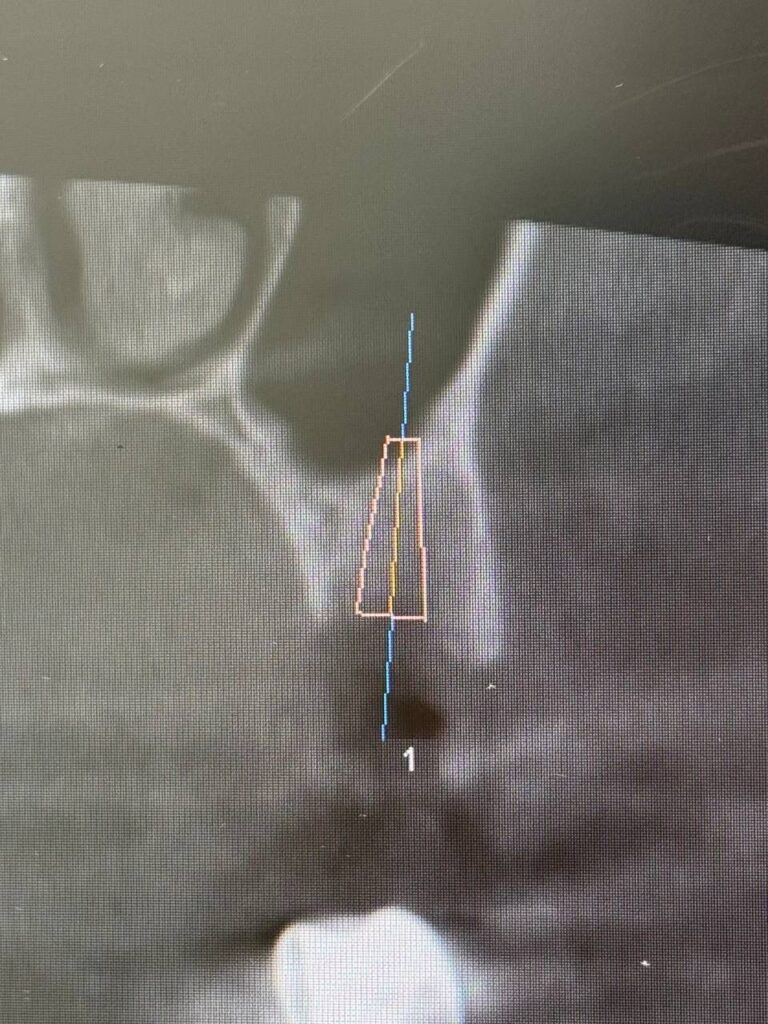

Специализация: терапия(эндодонтия), ортопедия, имплантология.